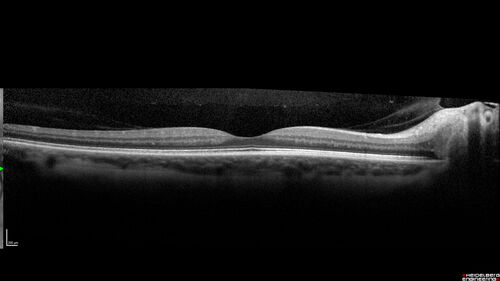

Ischemic Optic Neuropathy associated with GLP-1 Agonist

48 year old female woke up with blurry vision inferiorly in the right eye. the right optic nerve isnoted to be swollen. She does not have any pain with eye movements. The left eye is OK.

Medical History: Migraines

Surgical History: LASIK OU (2006)

Systemic Meds: Mounjaro (tirzepatide) injection qweekly since 8/2024, Prozac, Nexium, Sumatriptan.

VA OD: Dcc 20/20

VA OS: Dcc 20/16-1